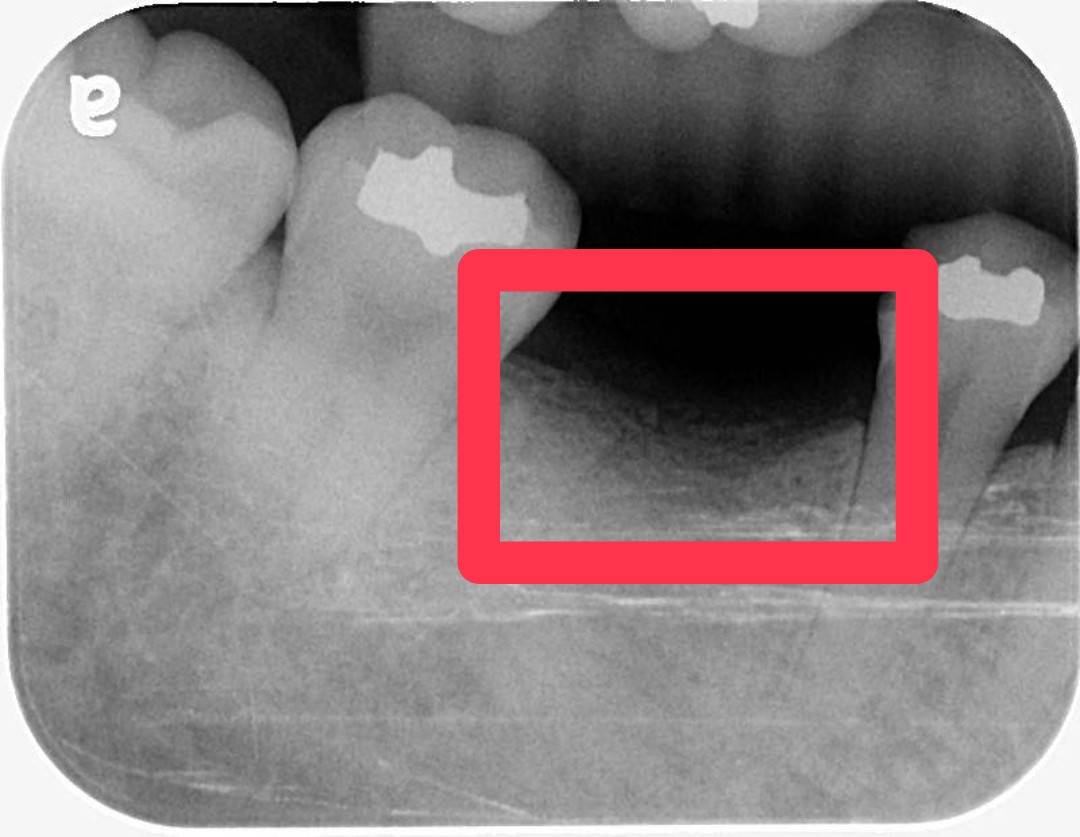

植牙後沒多久,植體出現脫落,

周圍骨頭也逐漸萎縮,

X光影像上只剩下一片明顯的黑影…